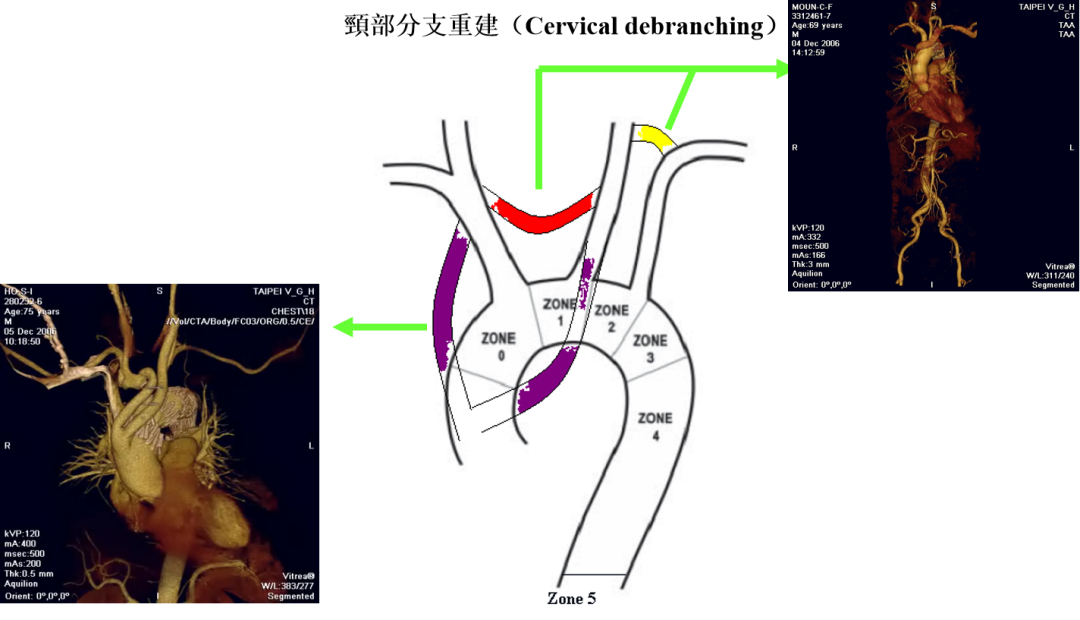

主动脉弓部病变的腔内治疗,长久以来被视为血管外科的“雷区”。在TEVAR(胸主动脉腔内修复术)中,为了获得足够的锚定区(Landing Zone)而覆盖弓部分支(如左锁骨下动脉LSA),往往伴随着卒中、截瘫及上肢缺血的风险。然而,随着TAG®Thoracic Branch Endoprosthesis (TBE) 在2024年底获得中国台湾TFDA批准,以及其在美国相继获得Zone 2(2022年)及Zone 0/1(2025年6月)的FDA批准,这一困境正在被打破。

回顾主动脉弓部疾病的治疗史,我们经历了从开放手术到腔内微创的漫长跨越。

传统术式的局限

在TEVAR时代,处理弓部病变主要依赖外科去分支(Surgical Debranching)。无论是颈部的旁路搭桥,还是开胸的复合手术(Hybrid),亦或是心外科的“象鼻干(Frozen Elephant Trunk)”技术,虽然有效,但创伤大、恢复期长,且面临吻合口出血及神经损伤的风险。

腔内技术的“野路子”

随着腔内技术的发展,烟囱(Chimney)技术和术中开窗(On-Table Fenestration)曾一度流行。然而,这些技术往往伴随着较高的内漏(Endoleak)发生率和支架闭塞风险,且操作复杂,极度依赖术者的经验。